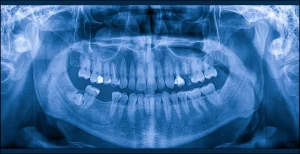

パノラマX線写真

パノラマX線写真は、口の中全体を一枚の画像で確認できるものです。

歯はU字型に並んでいるため、正面からの撮影では全体を把握できませんが、パノラマX線写真では上顎から下顎まで左右の歯列やあごの骨の状態を平面的に確認できます。

これにより、親知らずの有無や生える向き、歯の本数や配置の異常などを把握することができます。

また、大きな虫歯や歯根の異常、人工物の適合状況、歯の亀裂や割れ、歯石の付着具合、顎骨の状態も確認可能です。

デンタルX線写真ほど細かい確認は難しいものの、口腔全体のバランスや大きな異常を把握するのに適した検査です。